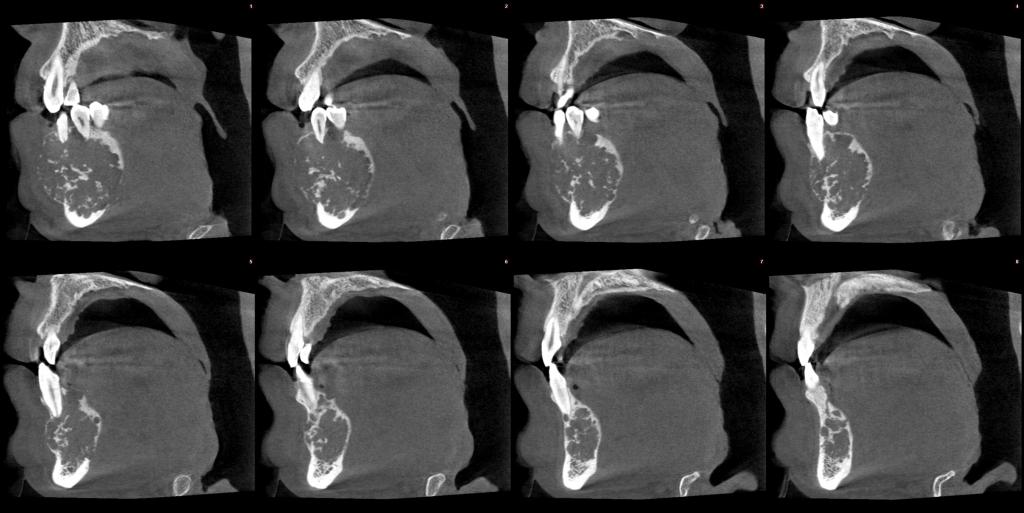

颅颌面CBCT

诊断范围涉及牙体牙髓病、牙周病、阻生牙/多生牙定位、种植牙术前CT评估分析、颞下颌关节CT诊断分析、,颌骨及涎腺疾病、颌面发育畸形、正畸治疗辅助诊断等大部分颌面部疾病,为临床医疗提供强有力的支持。